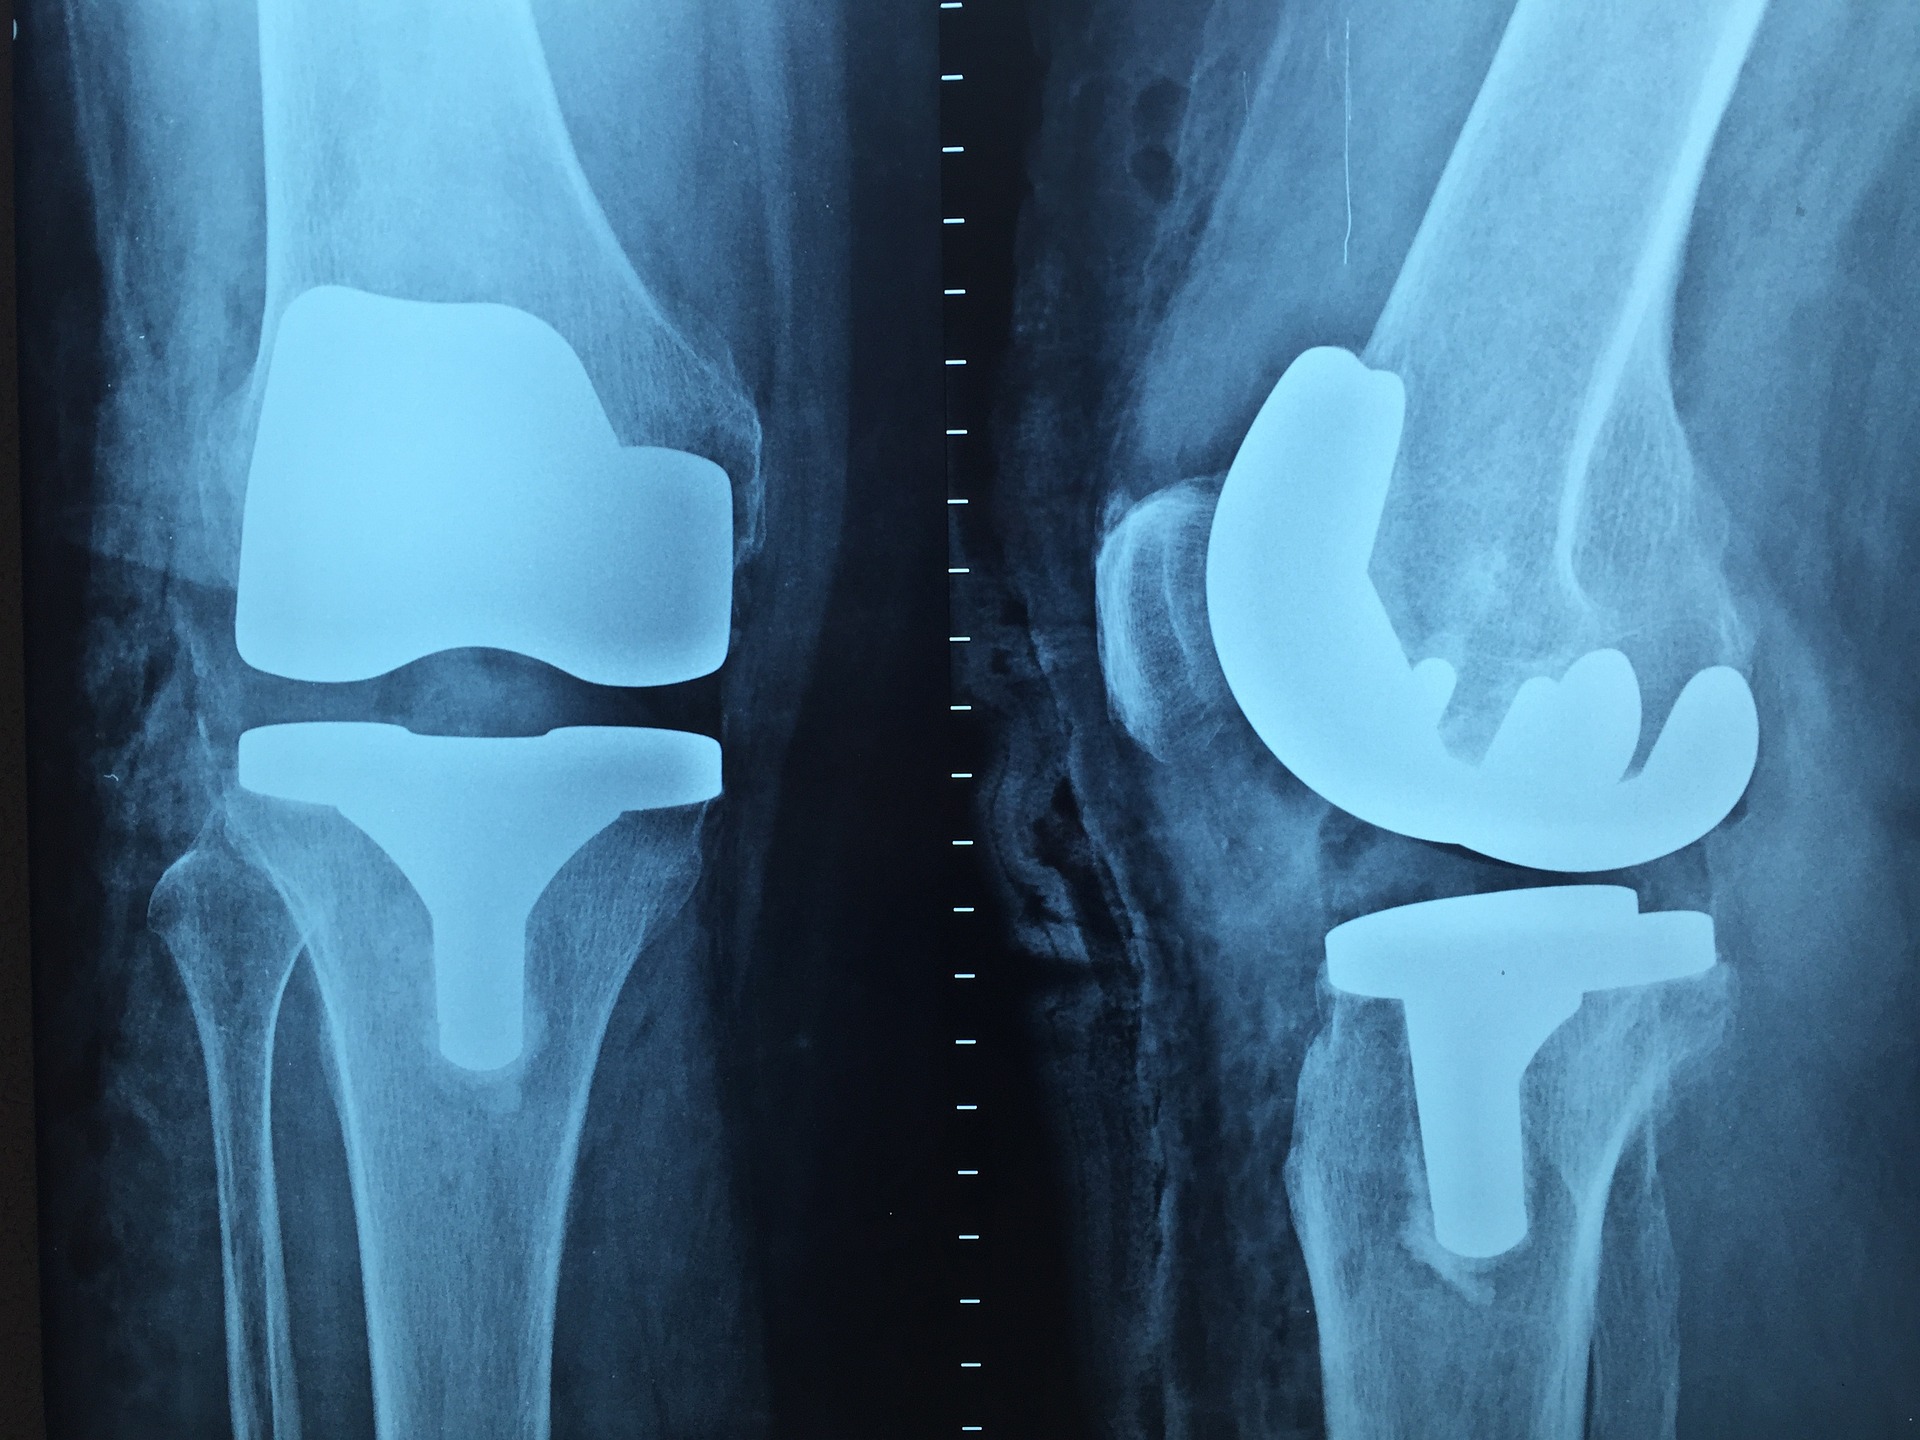

Geossa Guatemala cuenta con una amplia gama de implantes para traumatología reconocidos globalmente. Los productos comercializados son fabricados y diseñados con una tecnología avanzada; enfocados a ser funcionales, de fácil colocación y auxiliares en el proceso de recuperación . La calidad y seguridad son la vida de los productos.